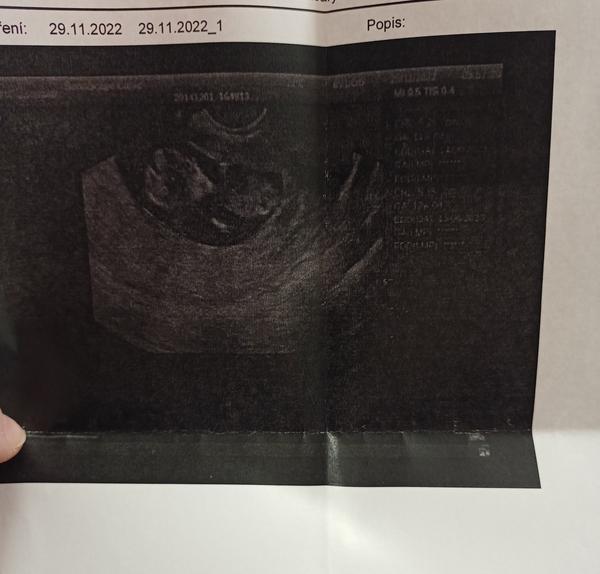

Tak už mám po kontrole srdíčko bylo a bilo ❤️ a odpovídám 8tt 🙂)